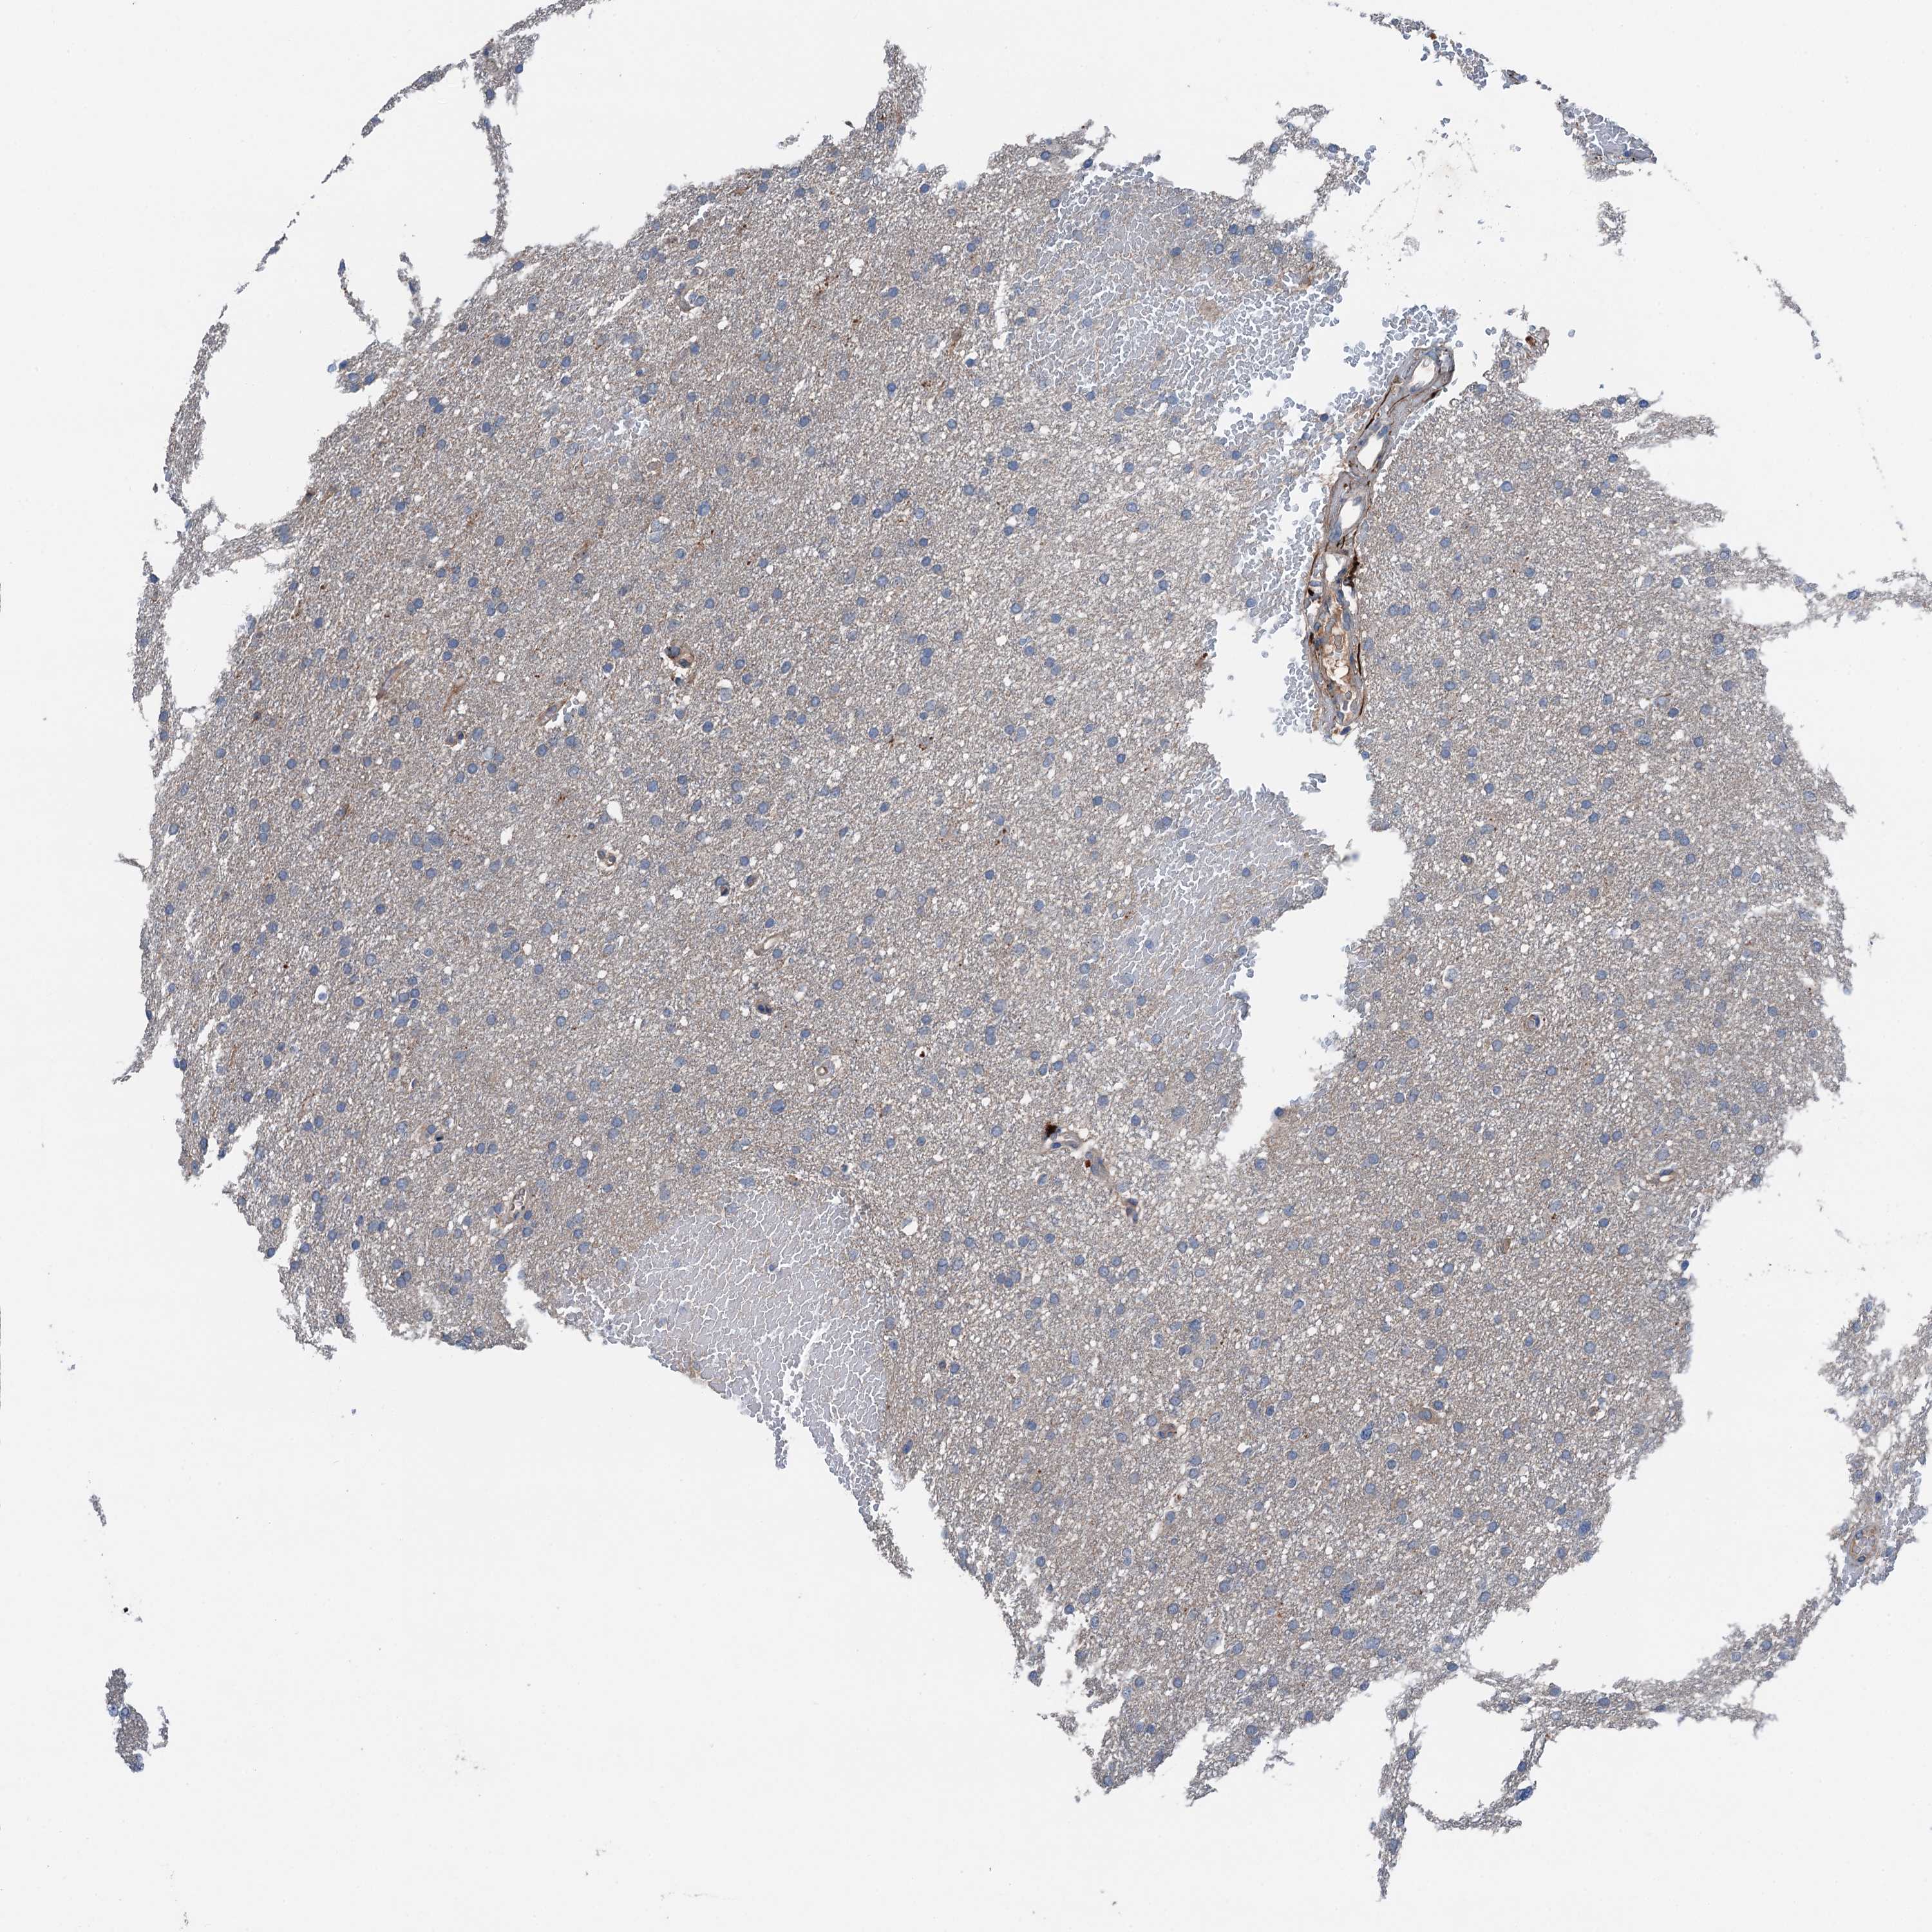

GLIOMA - Protein expressioni

A mouse-over function shows sample information and annotation data. Click on an image to view it in a full screen mode. Samples can be filtered based on level of antibody staining by selecting one or several of the following categories: high, medium, low and not detected. The assay and annotation is described here.

Note that samples used for immunohistochemistry by the Human Protein Atlas do not correspond to samples in the TCGA dataset.

Antibody stainingi

Antibody staining in the annotated cell types in the current human tissue is reported as not detected, low, medium, or high, based on conventional immunohistochemistry profiling in selected tissues. This score is based on the combination of the staining intensity and fraction of stained cells.

Each image is clickable and will lead to virtual microscopy that enables deeper exploration of all samples and also displays staining intensity scores, fraction scores and subcellular localization as well as patient and tissue information for each sample.

Antibody HPA041015

Staining

High

Medium

Low

Not detected

Intensity

Strong

Moderate

Weak

Negative

Quantity

>75%

75%-25%

<25%

None

Location

Nuclear

Cytoplasmic/membranous

Cytoplasmic/membranous,nuclear

Glioma, malignant, High grade

Glioma, malignant, Low grade